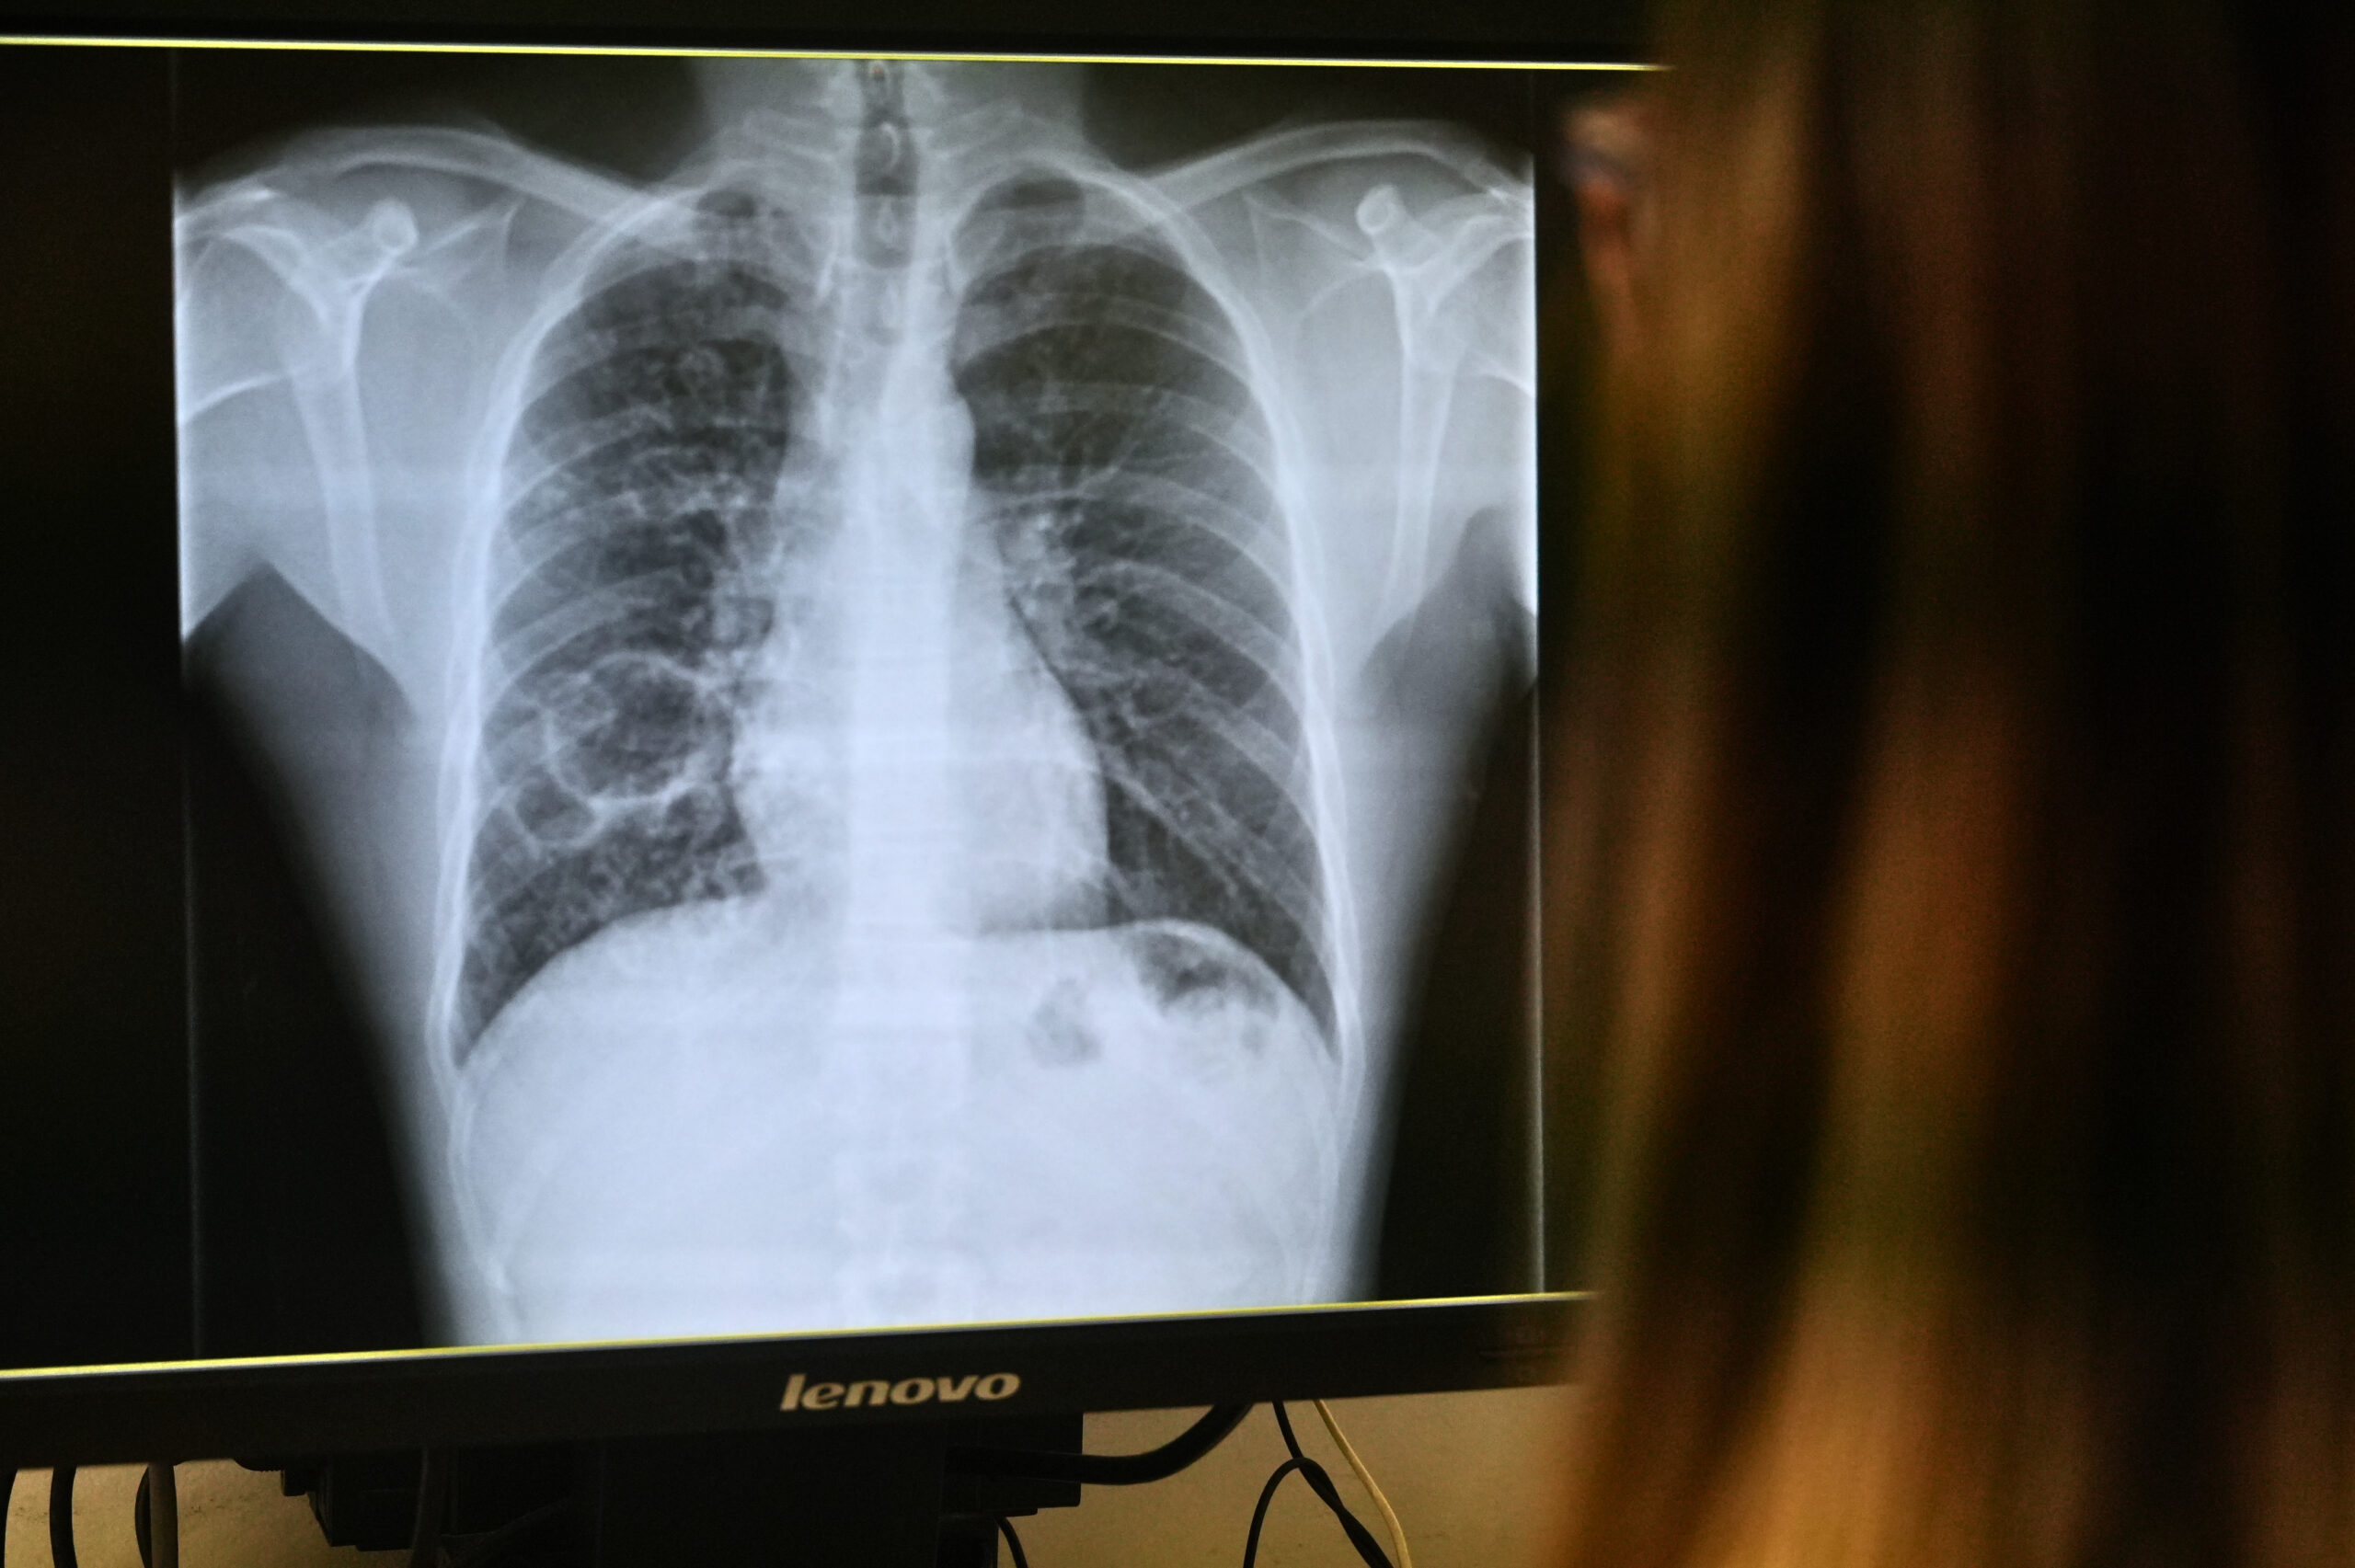

La tuberculosis afecta principalmente al pulmón, aunque también puede tener una afectación extrapulmonar. Solo las personas con afectación pulmonar activa son transmisibles, ya que es en el pulmón donde la bacteria se multiplica en gran cantidad y puede expulsarse al aire.